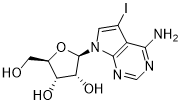

馬鞍山致研生物醫(yī)藥科技有限公司成立于馬鞍山市鄭浦港新區(qū)現(xiàn)代產(chǎn)業(yè)園。公司專(zhuān)注于生物小分子、醫(yī)藥中間體相關(guān)產(chǎn)品的研發(fā)和生產(chǎn),產(chǎn)品主要包括DNA亞磷酰胺單體、RNA亞磷酰胺單體、特殊單體以及按照客戶(hù)要求定制的RNA和DNA,并且公司提供定制合成等方面的研究服...

馬鞍山致研生物醫(yī)藥科技有限公司成立于馬鞍山市鄭浦港新區(qū)現(xiàn)代產(chǎn)業(yè)園。公司專(zhuān)注于生物小分子、醫(yī)藥中間體相關(guān)產(chǎn)品的研發(fā)和生產(chǎn),產(chǎn)品主要包括DNA亞磷酰胺單體、RNA亞磷酰胺單體、特殊單體以及按照客戶(hù)要求定制的RNA和DNA,并且公司提供定制合成等方面的研究服...